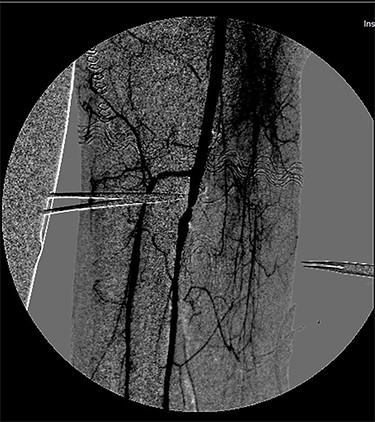

At the Doppler examinations after 2 and 12 months, triphasic-flow of the entire vascular artery axe of the lower right limb was detected (Fig. 4).

Duplex ultrasound made after 2 months, showing triphasic flow of the right popliteal artery.